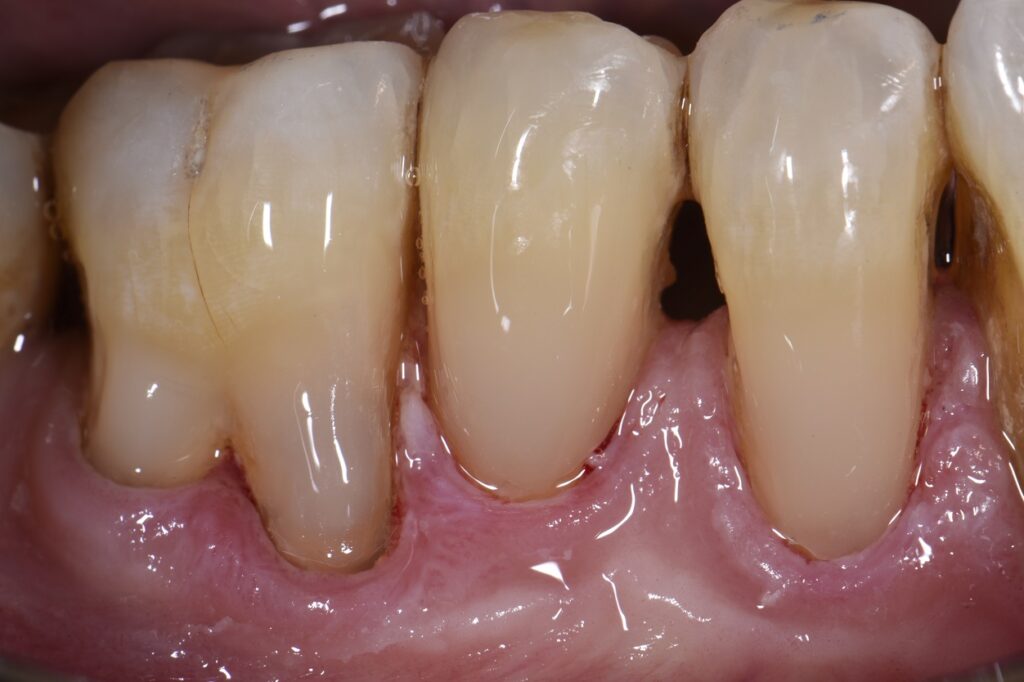

From www.clarencetam.co.nz

Root Abrasion Lesions restored with noninvasive dentistry What Is Denture Abrasion Dental abrasion is a condition that occurs when the tooth enamel wears away due to. It can occur due to various factors, such as aggressive tooth brushing, abrasive toothpaste, bruxism (teeth grinding), and diet a dental abrasion is a loss of tooth structure that occurs when the tooth is cleaned with a toothbrush or other cleaning device. this. What Is Denture Abrasion.